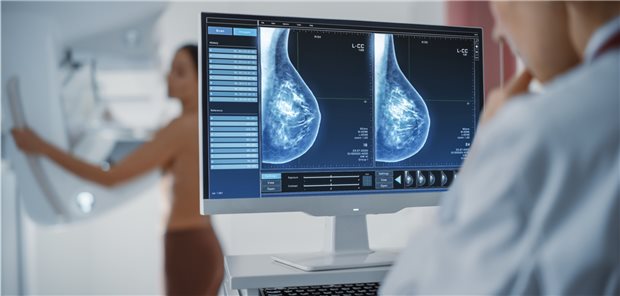

3,3 Millionen gesetzlich Versicherte waren im Jahr 2019 an Krebs erkrankt. Die Diagnoseprävalenz hat seit 2010 deutlich zugenommen, meldet das Zi im Versorgungsatlas. Das bringe Herausforderungen auch für Hausärzte.

Aktuelle Daten zu Krebserkrankungen in Deutschland hat das Robert Koch-Institut veröffentlicht. Der Bericht liefert zusätzliche Hinweise auf verspätete Krebsdiagnosen im ersten Corona-Lockdown.